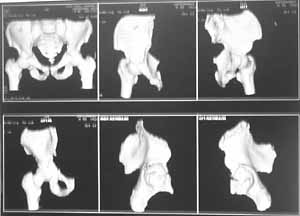

He has bilateral bicolumn acetabular fracture. At present on bilateral skin traction. I am attaching available images. CT of acetabulum planned after patient is out of ventilator.

I am attaching the reconstructed picture from the CT on this case.